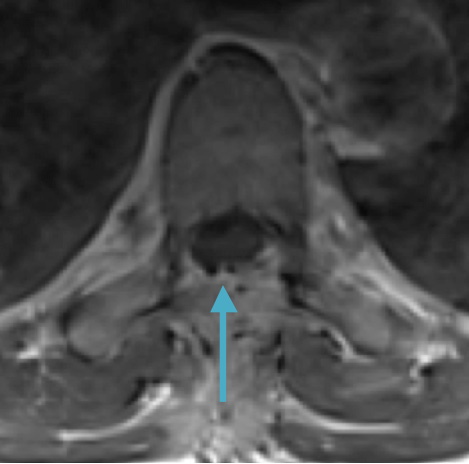

Postoperative MRI T2 illustrating the restoration of CSF surrounding the cord (blue arrow)